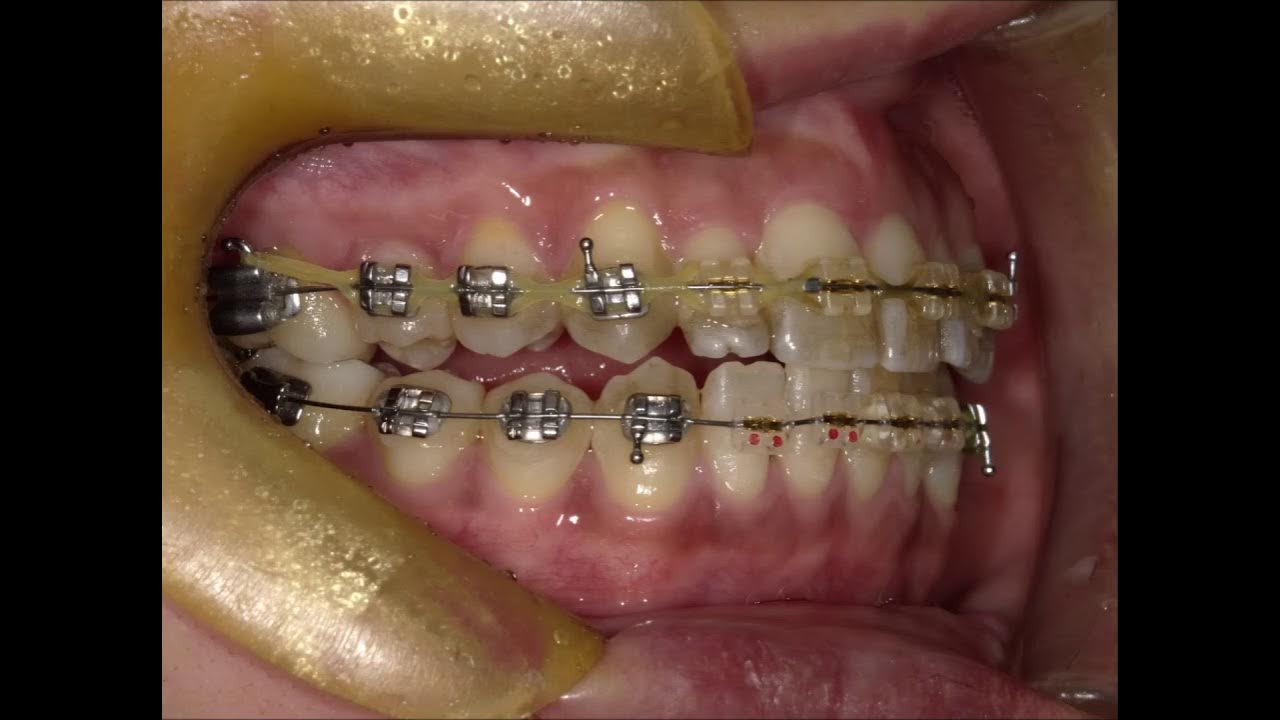

From prestige-dental-care.com.my

Orthodontic A case with fix appliance 03 Fixed Orthodontics Slideshare this document discusses fixed orthodontic appliances. It notes that fixed appliances are attached directly to teeth and can precisely. Fixed appliances removable n tipping only n no control. Overbite reduction by intrusion of incisors. fixed orthodontic appliances dent 657. steps for orthodontic emergencies: We are prepared to handle the most common orthodontic emergencies. indications for the. Fixed Orthodontics Slideshare.